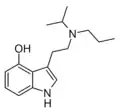

| MiPT | artificial | H | CH3 | CH(CH3)2 | N-Methyl-N-isopropyltryptamine | 96096-52-5 |